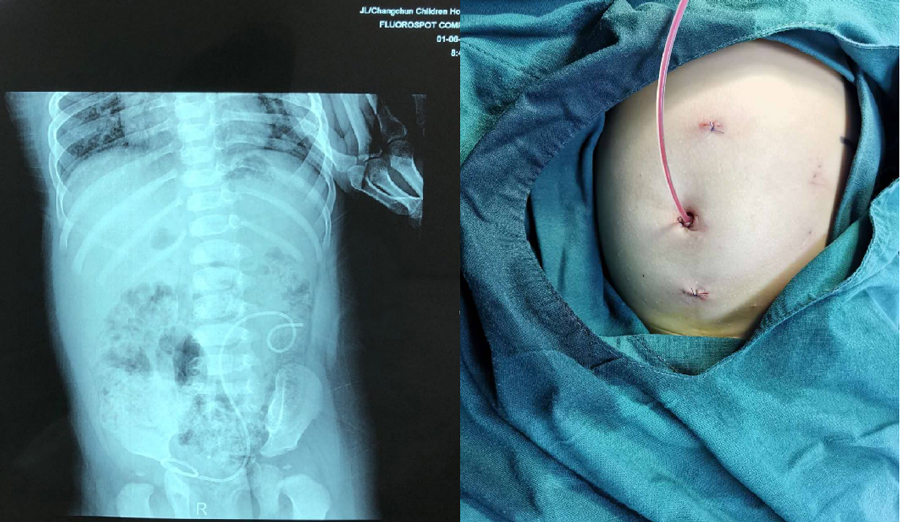

熟练应用腹腔镜微创手术:用于肾盂输尿管连接部梗阻、重复肾半肾切除、高位隐睾、精索静脉曲张、肾切除等,使损伤减小、病程缩短、早期恢复正常活动。2018年开展儿童性发育不良治疗,填补了我省男童外生殖器发育迟缓治疗的空白。

单孔腹腔镜引导下经阴囊治疗高位隐睾